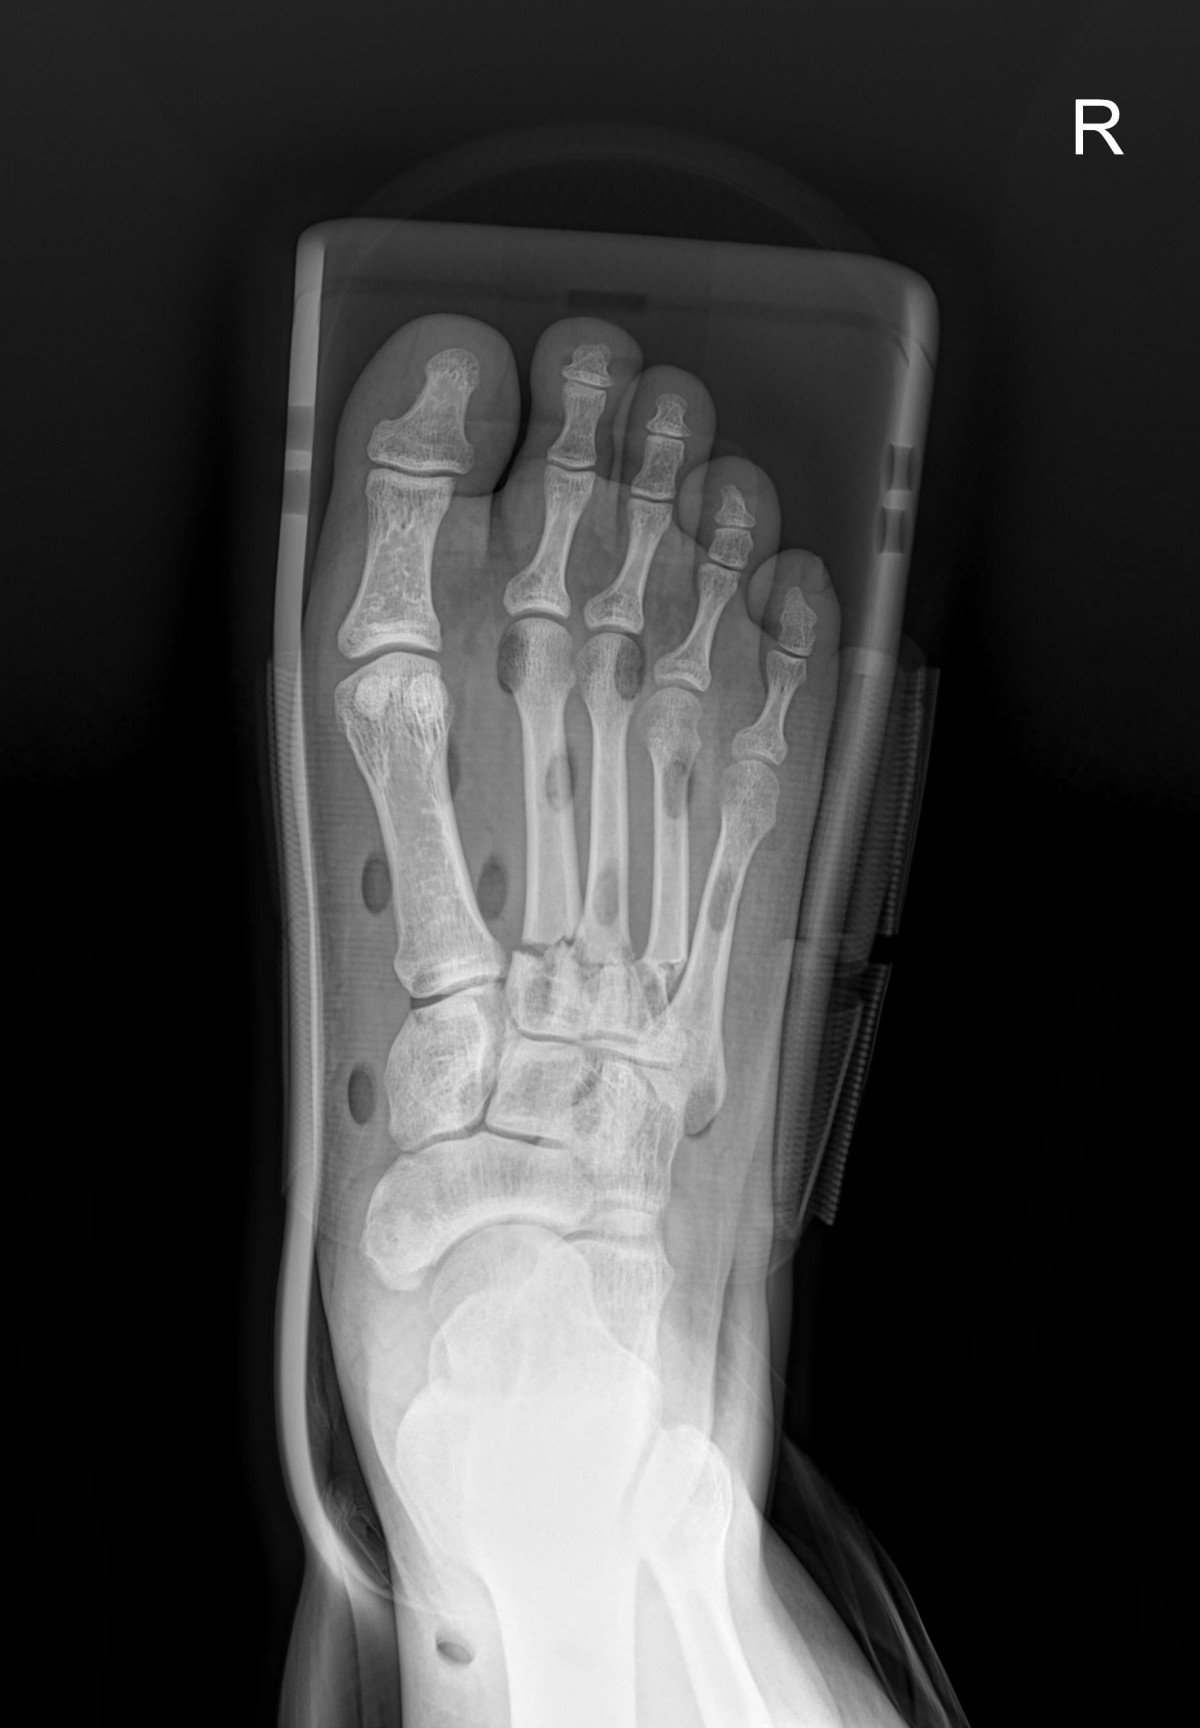

최원락원장님 발등 골절 수술 정윤O 환자

32341c324db2d176f34ec014ac758183_1729061002_0237.jpg

32341c324db2d176f34ec014ac758183_1729061015_679.jpg